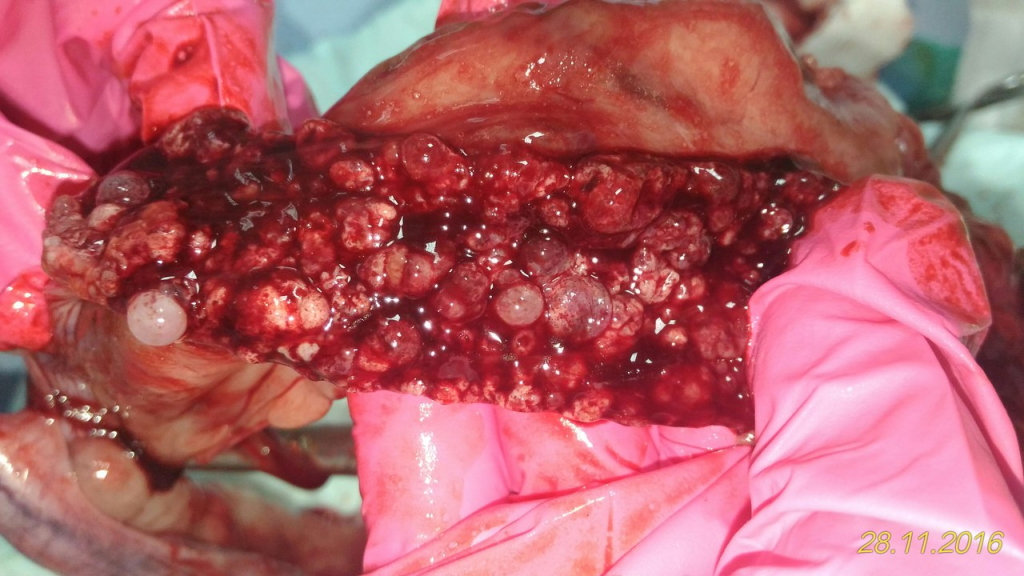

После постановки диагноза и стабилизации пациента лечение возможно только хирургическое-овариогистеректомия. (Рис. 3)

Рис.3 Матка, после овариогистеректомии. Эндометрий представляет собой неравномерно плотно утолщенную массу с множественными кистами.